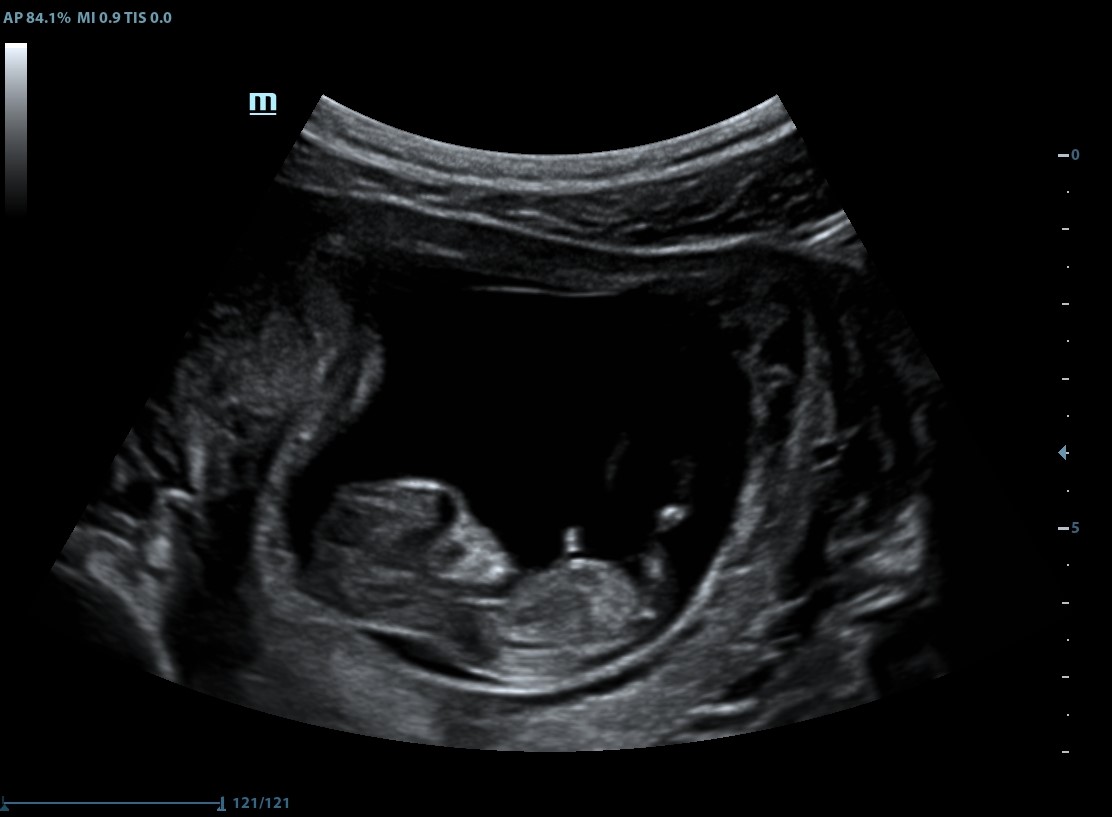

Ogledujem si te na fotografiji, prižgem ti svečko in razmišljam o tebi. Kar naenkrat me prešine misel. Posnetek! Imam ultrazvočni posnetek! Srce mi začne hitreje biti. Spomnil si me. Kako sem lahko pozabila na to? Med nosečnostjo mi je ginekolog poslal ultrazvočni posnetek ene od preiskav.

Gledam, kako si brcal. Spet slišim utrip tvojega srca. Kako zelo boli! Ko bi vsaj lahko vrnila čas nazaj.